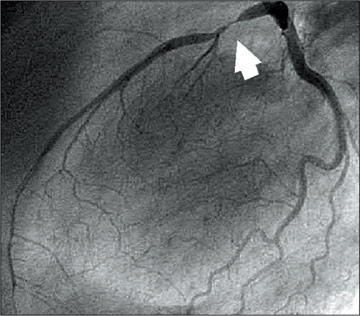

Bei der Koronarangiographie werden über die Venen (beginnend in Leiste oder Ellenbogen) dünne Schläuche (Katheter) in die Herzkammern geführt, so dass Röntgen-Kontrastmittel direkt in die Herzkranzgefäße gespritzt werden kann. In der Röntgenaufnahme ist gut zu sehen, wo in den großen Herzkranzgefäßen ein Engpass (Pfeil) oder gar ein Verschluss aufgetreten ist. |